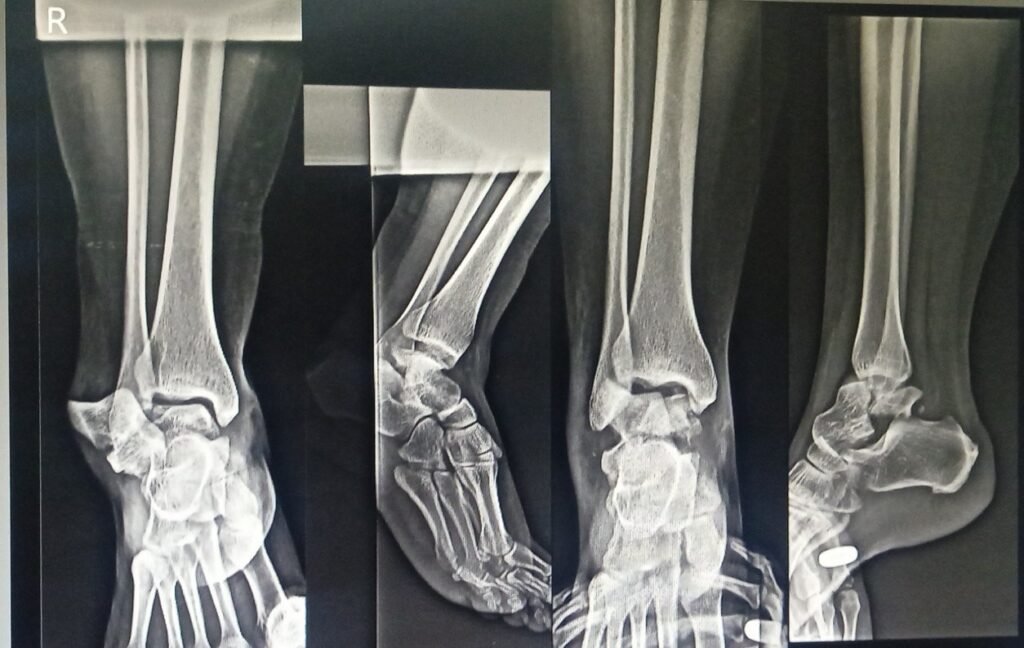

Minimal Invasive Talus Fracture

• Minimally invasive talus fracture surgery uses imaging guidance and small instruments for precise bone alignment and secure fixation.

• Small incisions reduce soft tissue damage, helping preserve blood supply and lower risk of complications during healing.

• This approach decreases postoperative pain, swelling, and infection risk compared to traditional open surgical methods.

• Faster recovery enables early ankle movement, improving mobility and supporting better functional outcomes over time.

• Proper fixation and alignment promote long-term joint stability, reducing the chances of arthritis and chronic ankle issues.